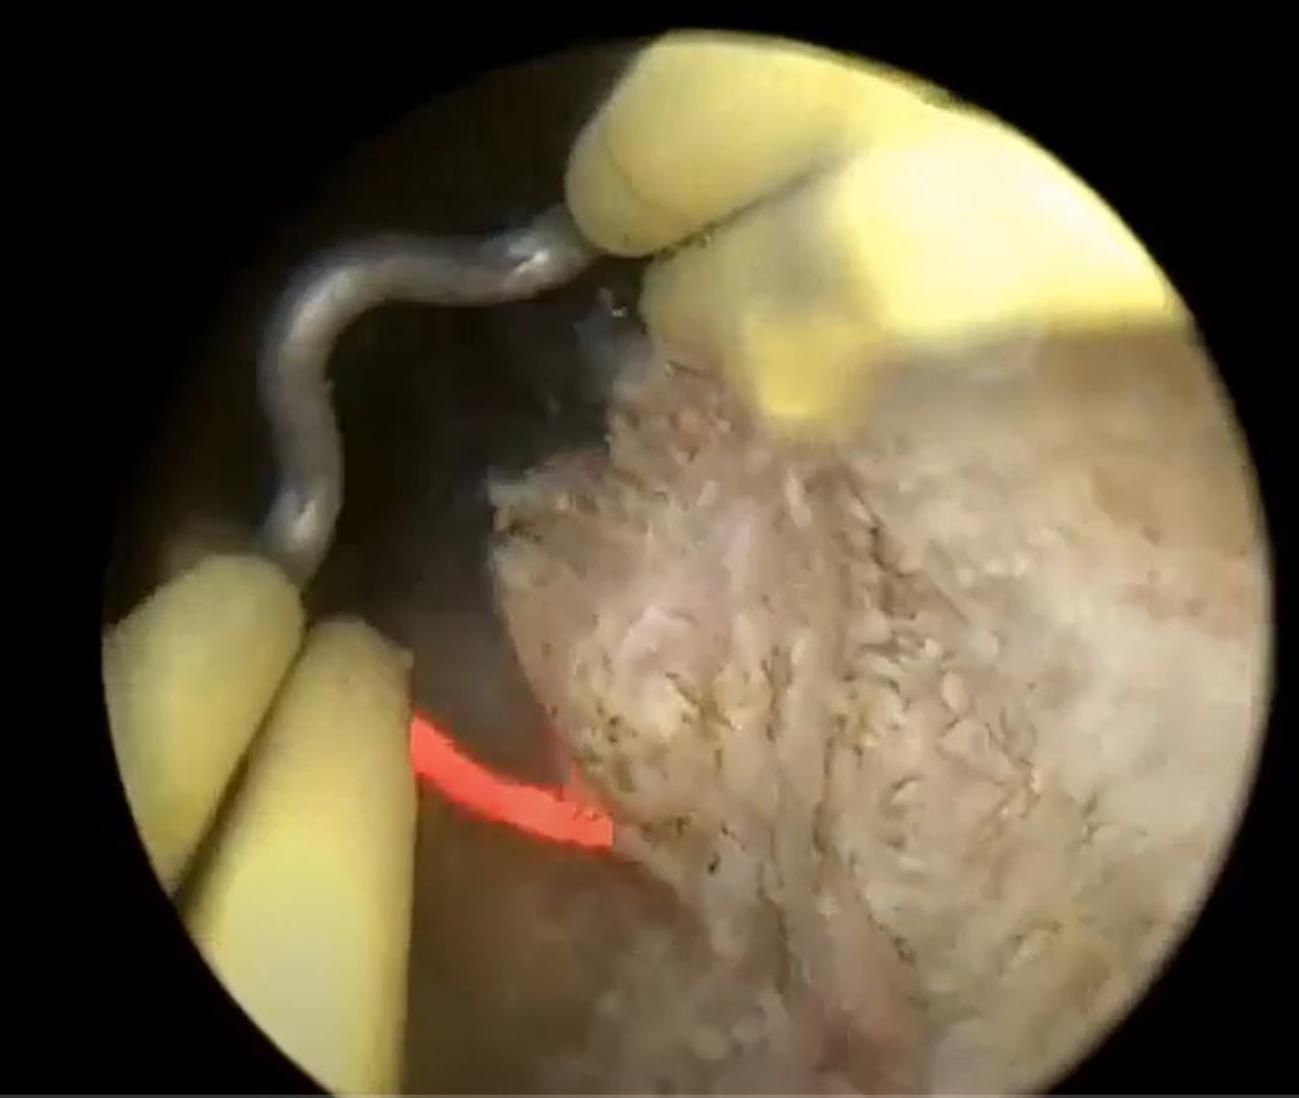

Через трубку резектоскопа подается ирригационная жидкость (физраствор) для охлаждения и очистки рабочей области от крови и срезанной ткани. Срезанные кусочки ткани под действием струи ирригационной жидкости выносятся в мочевой пузырь, где накапливаются до окончания операции. Удаляются они из мочевого пузыря через резектоскоп или отсасываются с помощью шприца Тьефеля. Крупные фрагменты удаляются с помощью специального захвата.

На конце резектоскопа установлена видеокамера и осветительный прибор, что позволяет отображать весь процесс на экране большого монитора.

В резектоскоп можно вставлять различные рабочие инструменты и петли различной формы и размера. Для среза ткани петля разогревается переменным током величиной 0,3...1,5 А и частотой 300-500 кГц. Это позволяет избежать стимуляции током мышц или нервов. Петля разогревается до красного или белого свечения в режиме резания при напряжении 100-300 В и до 200-400 В в режиме коагуляции (остановки кровотечения путем запаивания сосудов). Напряжение и ток подаются в форме импульсов с регулируемой скважностью. Регулировка параметров может выполняться оперативно в процессе операции.